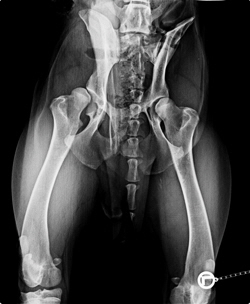

Marlos Hftgelenke vor und nach der DBO

Azads Becken ist abgeheilt. Die Gelenkkapsel rechts ist noch locker und wird im Laufe der Zeit immer fester werden. Die Steilstellung des rechten Oberschenkelkopfesist nachder DBO verschwunden. Azad ist topfit und htet seine Familie.

DBO, TPO  beidseitig Balou